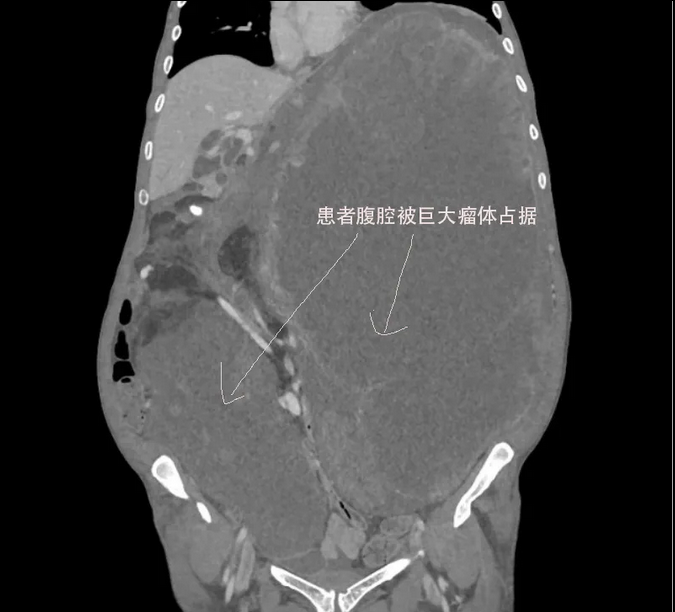

📍 Facing a twice-recurrent 17.5kg Leiomyosarcoma, a surgeon’s first priority is not the incision, but a "strategic gamble" of clinical logic.

🚫 We also ruled out purely conservative care, as the 32.5cm mass posed an imminent lethal compressive threat.

📉 Despite imaging showing a "frozen abdomen," palpation revealed a resilient abdominal tone. This was a critical signal: the tumor likely possessed an intact pseudo-capsule. As long as the capsule wasn't extensively infiltrated, a dissection plane existed.